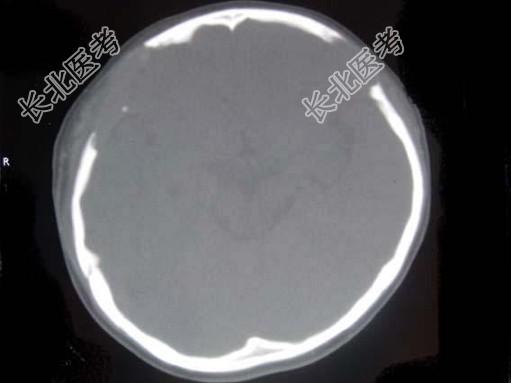

- 单项选择题女,22岁。反复头痛伴双下肢水肿10余年, 有多饮、多尿,近1个月来咳嗽, 呈阵发性,有时伴有脓痰, 低热,头部可触及柔软的软组织肿块及边缘不规则的骨缺损, 四肢及躯干皮肤可见散在出血点,双下肢凹陷性水肿, 结合所提供的图像,最可能的诊断是 ( )

A、韩-雪病

B、非骨化性纤维瘤

C、骨巨细胞瘤

D、骨纤维结构不良

E、内生软骨瘤